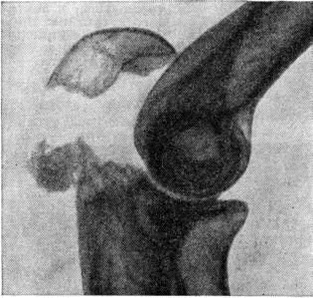

Основной рентгенологическое признак нарушения целости кости — линия Переломы Большое диагностическое значение имеет смещение отломков, наличие которого настолько бесспорно доказывает нарушение целости кости, что надобность в дифференциальной диагностике отпадает. Как бы подробно ни была описана рентгенологическое картина Переломы, наиболее полное и правильное представление о степени и характере смещения отломков врач может составить лишь при непосредственном просмотре снимков. Захождение отломков одного за другим при продольном смещении на рентгенограмме в одной проекции может сопровождаться наслоением теней концов отломков — так называемый суперпозицией теней. В этом случае точное определение смещения отломка возможно на основании данных снимков во второй проекции. При Переломы плоских костей (лопатка, ребра, таз и другие), при которых по техническим причинам производство снимка во второй проекции затруднено, суперпозиция отломков часто является единственным достоверным признаком Переломы Распознавание продольных смещений с расхождением отломков обычно не представляет каких либо затруднений. Подобного рода смещения наблюдаются при Переломы надколенника с разрывом связочного аппарата, локтевого отростка, вертелов бедра, отрывах костных выступов, к которым прикрепляются мышцы, сокращающиеся при повреждениях и приводящие к расхождению. Интерпозиция мягких тканей между отломками костей при рентгенологическое исследовании не распознается. Различные виды Переломы в наиболее информативных проекциях представлены на рисунок 4—11.

Рис. 5.

Боковая рентгенограмма локтевого сустава: оскольчатый перелом локтевого отростка с расхождением отломков.